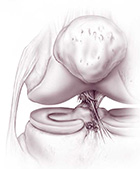

Nei casi in cui i sintomi dolorosi persistono o nei casi previsti, le rotture meniscali sono trattate anch’esse artroscopicamente con ottimi risultati. Le lesioni più periferiche (nella cosiddetta “zona rossa”) hanno qualche chances di guarire e per questo motivo possono essere suturate (nei pazienti giovani). Le rotture più comuni, tuttavia, avvengono nella zona più interna, la meno vascolarizzata (“zona bianca”); non avendo possibilità di cicatrizzarsi, la parte del menisco rotta viene semplicemente asportata.

In casi estremamente selezionati e in pazienti giovani con richieste funzionali elevate, i trapianti di menisco possono avere una indicazione.